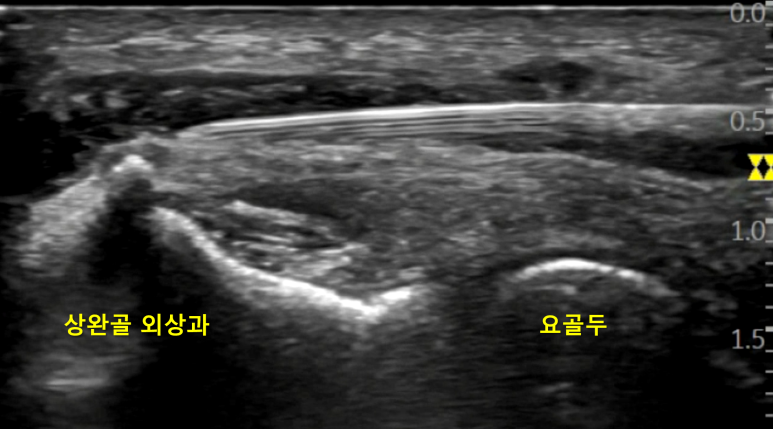

이것을 한의 초음파 또는 경혈 초음파라고 부릅니다.** 예를 들어 팔꿈치 바깥쪽 외측상과염, 즉 테니스 엘보는 한의학의 경락 변증상 수양명에 문제가 있다고 진단하는데요.**

한의학에서 테니스 엘보우에 흔히 활용하는 혈 자리는

수양명경락의 곡지혈(LI11)과 수삼리혈(LI10)입니다.

두 혈자리 모두 요골동맥과 요골신경이 지나가는 고위험 경혈이므로,

약침이나 도침 같은 특수침을 시술할 때 각별한 주의가 필요합니다.

저와 문지현 원장님 모두 부산대 오명진 교수님께 경혈 초음파를 전수받아 10년 넘게 한의 초음파에 매진해왔습니다. 한번 손을 대면 끝을 봐야하는 성격이라 매일 도 닦는 마음으로 정진하고 있는데요. 그동안 한의 초음파의 실효성에 대해 한번도 의심해본 적이 없습니다. 누가 뭐라 하든, 저는 묵묵히 제 길을 가볼 생각입니다. 곡지혈(LI11), 초음파 유도하 약침술 정형외과에서 테니스엘보로 진단받고 내원하신 환자분의 곡지혈에 초음파 유도하 약침을 시술하는 영상입니다.